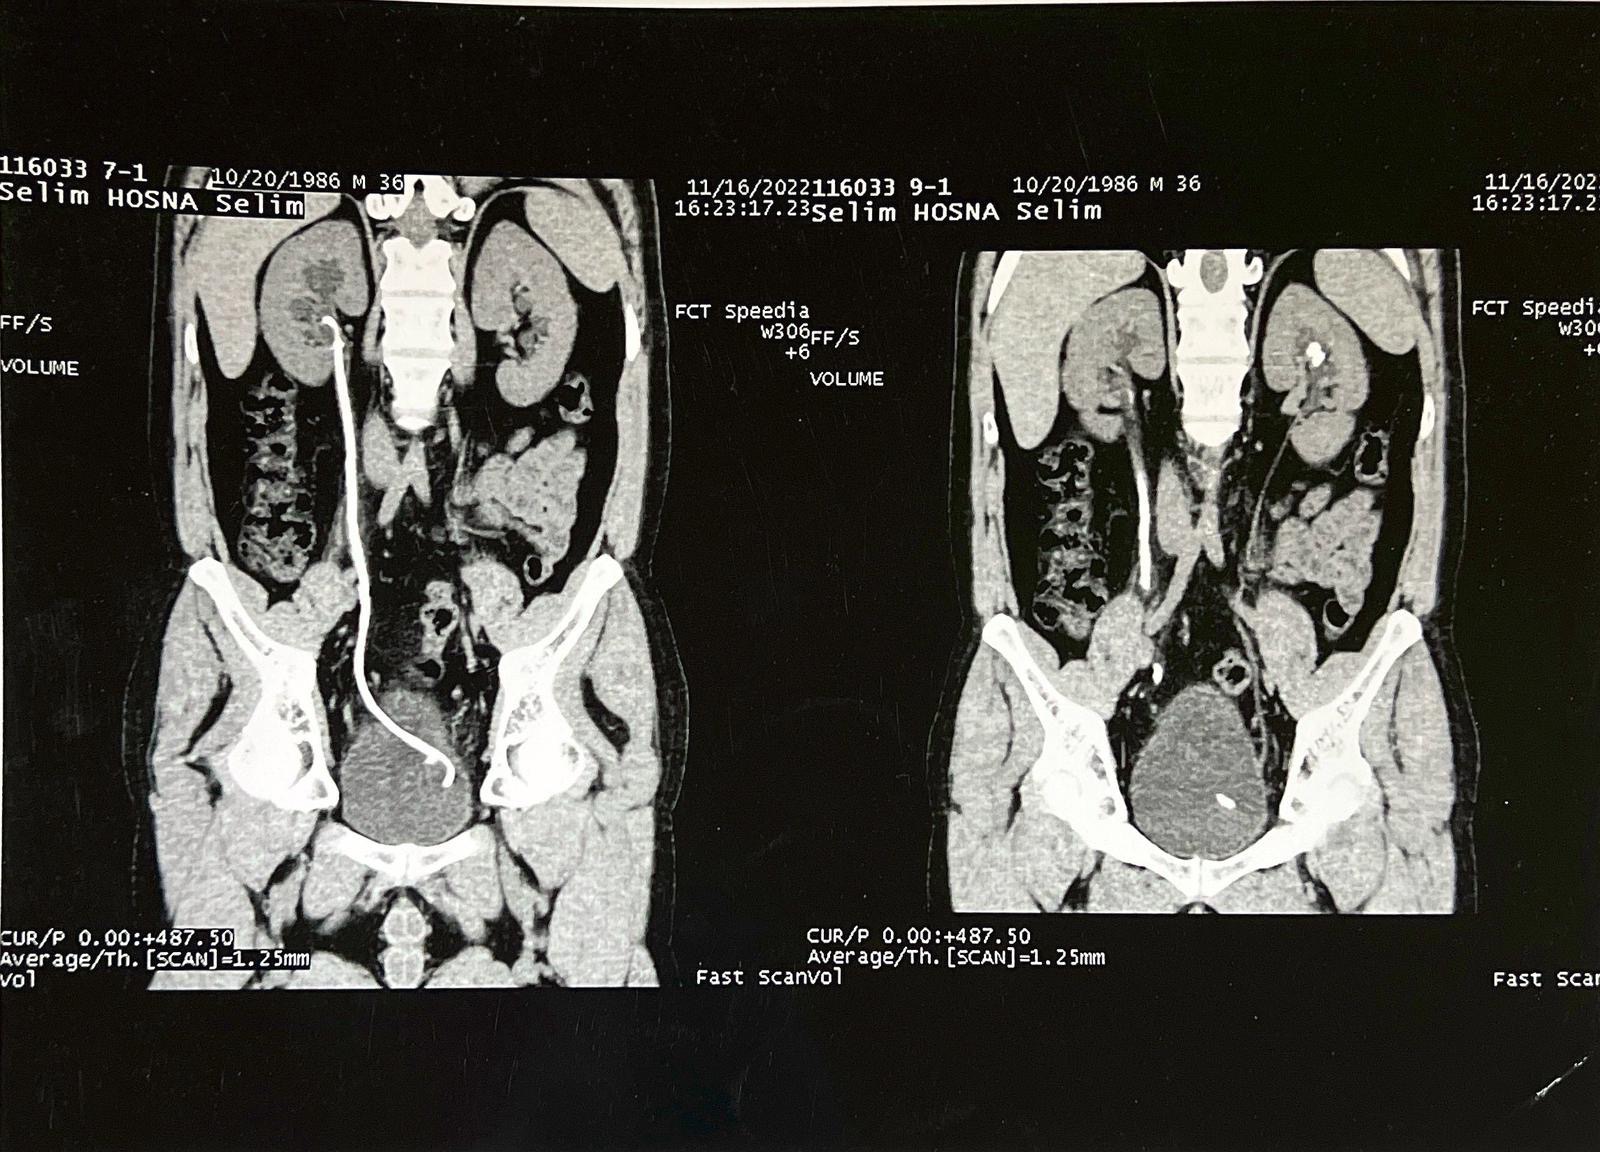

I am currently suffering from a severe kidney stone measuring four centimeters in length, a condition that is causing me excruciating pain on a daily basis. Due to the severely limited healthcare infrastructure in Gaza, there are no available facilities or specialists capable of performing the necessary surgical procedure to remove the stone.